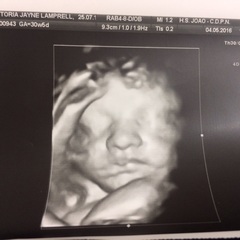

So hard to keep up I can't keep information in my head to continue chatting, but generally I need to up my water intake as well I get so many braxton hicks and baby is very low head down and enjoys punching my cervix. He moves loads when I sit and eat or drink anything but goes bananas lunch time and dinner time. I'm really suffering from pelvic ligament pain a lot more than last time it's really starting to affect me and mobility :( but had scan last week ( Portugal do 3 standard scans) and they do standard 3D scan and free pictures which is awesome

Vikki those pics are gorge too. These scans really are great. So nice to get the extra scan and 4d as standard.